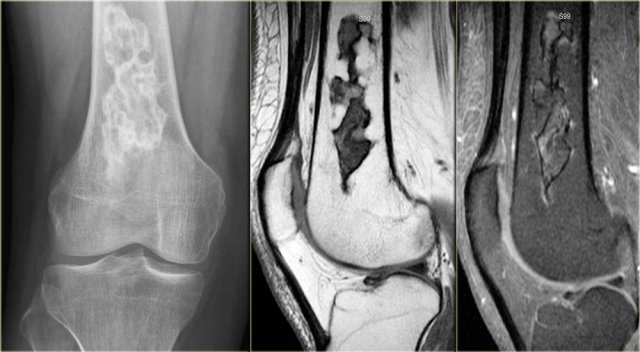

Here images of an osteosarcoma in the right femur.

It is barely visible within the bone, but an agressive periostitis is seen (arrow).

Continue with the MR-images.

The sagittal T1WI and Gd-enhanced T1W-image with fatsat show a large tumor mass infiltrating a large portion of the distal femur and extending through the cortex into the soft tissues.